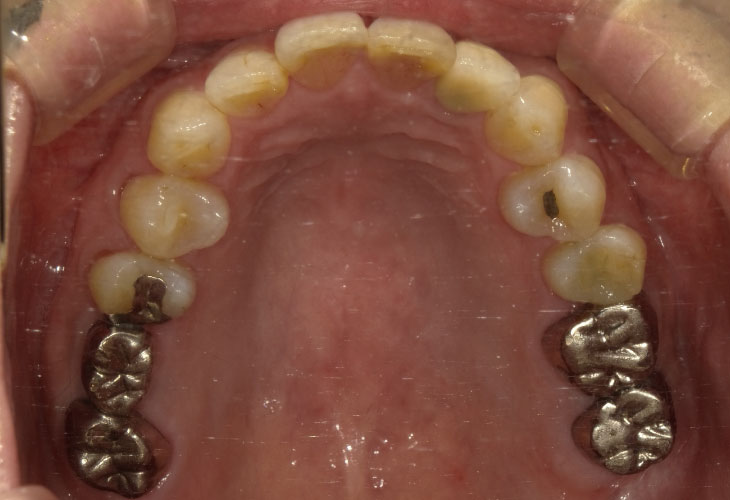

BEFORE

インプラント(右下6・7)

オールセラミックス(左上2)

E-MAX CAD(左上6・7)